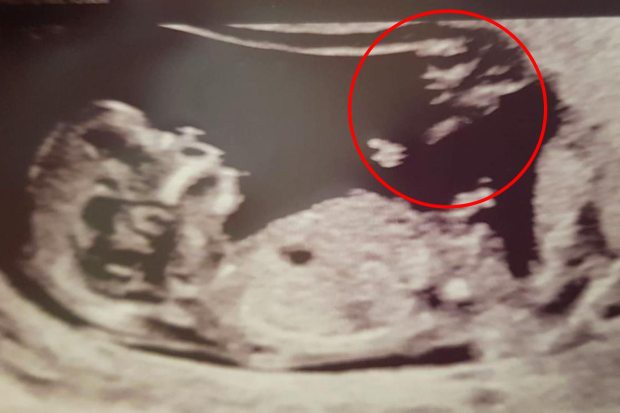

Не беременность, а чудо: на снимке УЗИ появился "ангел-хранитель"

| Пара из Англии, которая была уверена в том, что они никогда не смогут стать родителями, столкнулись с настоящим чудом. На фото, которое они получили после УЗИ, они увидели силуэт некого человека, который рукой указывал на будущего малыша. Будущие родители уверены в том, что это был "ангел-хранитель", сообщает портал PLANETANOVOSTI.COM со ссылкой на The Sun. Британи Кларк и Джеймсу Груверу исполнилось только 24 года. Но за это время что они вместе, пара практически свыклась с мыслью, что родить детей у них не получился. Девушке был поставлен диагноз эндометриоз. В этом случае клетки, которые составляют внутренний слой стенки матки, активно разрастаются. Это становится причиной кровотечений, болезненных ощущений и, соответственно, бесплодия. ![]() Некоторое время назад Британи очень плохо себя чувствовала. Джеймс сказал ей, чтобы она сделала тест на беременность. Они не могли поверить в увиденное, ведь тест оказался положительным. Но во время посещения УЗИ пара была удивлена еще раз. На фотоснимке в правом верхнем углу была четко замечена тень, которая имела форму человека с вытянутой рукой. Британи сразу же поделилась с родными снимком. Ее тетя сказал, что это "ангел-хранитель" ребенка, который на фотографии УЗИ указывает на него. |